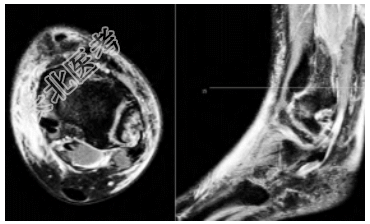

- [材料题] 患者,女,39岁,主诉“外伤致左踝部疼痛、活动受限1h”入院,就诊于日照市中医医院急诊外科。查体:左侧踝关节局部软组织肿胀压痛,后外侧压痛明显,踝关节活动受限,可触及足背动脉搏动,左侧下肢远端血运、感觉、活动未见明显异常。辅助检查:左侧胫腓骨(包括踝关节)X线片显示左侧腓骨远端骨折,骨折块在正位片被腓骨干遮挡(图1)。入院后完善踝关节CT检查,CT横断面显示左侧腓骨远端后侧骨折块,骨折块向胫骨侧移位,骨折线沿冠状面走形,左侧腓骨切迹为Ⅰ型,右侧腓骨切迹为C型(图2);CT矢状面显示左侧腓骨远端后侧骨折块,未累及腓骨干(图3)。CT三维重建显示左侧腓骨远端后侧类椭圆形骨折块,为明确有无下胫腓联合韧带断裂,完善MRI检查,MRI显示下胫腓前、后韧带均完整,下胫腓后韧带与骨折块相连(图4),牵拉骨折块向内侧移位,PDW序列显示下胫腓后韧带存在浅深两层且在部分层面存在融合。以上检查结果可明确诊断下胫腓后韧带腓骨端撕脱骨折。